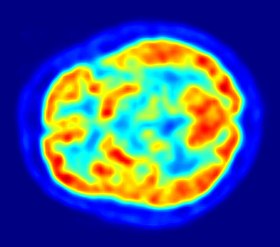

أشارت دراسة أمريكية بأن دماغ الإنسان تعمل بأقصى طاقتها عندما نكون في التاسعة والثلاثين ثم تبدأ بالتراجع بوتيرة سريعة بعد ذلك، حيث بعد سن الأربعين يعجز جسم الإنسان عن إصلاح الطبقة التي تغطى الخلايا العصبية، وأوضح علماء أن هذه الطبقة تشكل عازلاً وهي شبيهة بالغطاء البلاستيكى الذي يغطى الكوابل الكهربائية وتتيح الانتشار السريع للإشارات حول الجسد والدماغ [2]